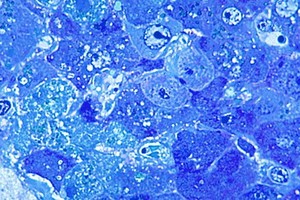

英十餘年來首次報告拉沙熱病例

#拉沙熱病毒